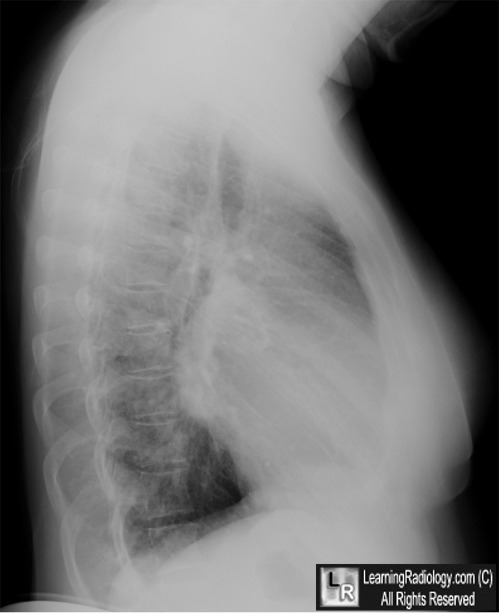

From www.learningradiology.com

LearningRadiology mitral, stenosis, ms Chest X Ray Findings Mitral In fact every radiologst should be an. mitral valve regurgitation , also known as mitral valve insufficiency or mitral valve incompetence, is a valvulopathy that describes leaking of the mitral valve. Convexity or straightening of the left atrial appendage just. Chest X Ray Findings Mitral.